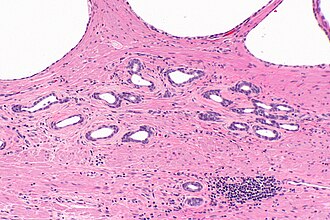

Atrophic prostatic glands. H&E stain. | |

| LM | glands typically have a jagged edges/prows (in cancer the glands tend to have round edges), gland density is usually lower than in prostate carcinoma (glands are not back-to-back), nuclei small & hyperchromatic, scant cytoplasm |

- Glands often have a jagged edges/prows (in cancer the glands tend to have round edges) - key feature.

- Gland density is usually lower than in prostate carcinoma, i.e. glands are not back-to-back - key feature.

- Atrophic glands are often hyperchromatic.[6]

- Scant cytoplasm - usually.

- Nuclei like normal, i.e. nucleoli uncommon.

- Should have two cell layers, i.e. epithelial and myoepithelial (may be difficult to see).